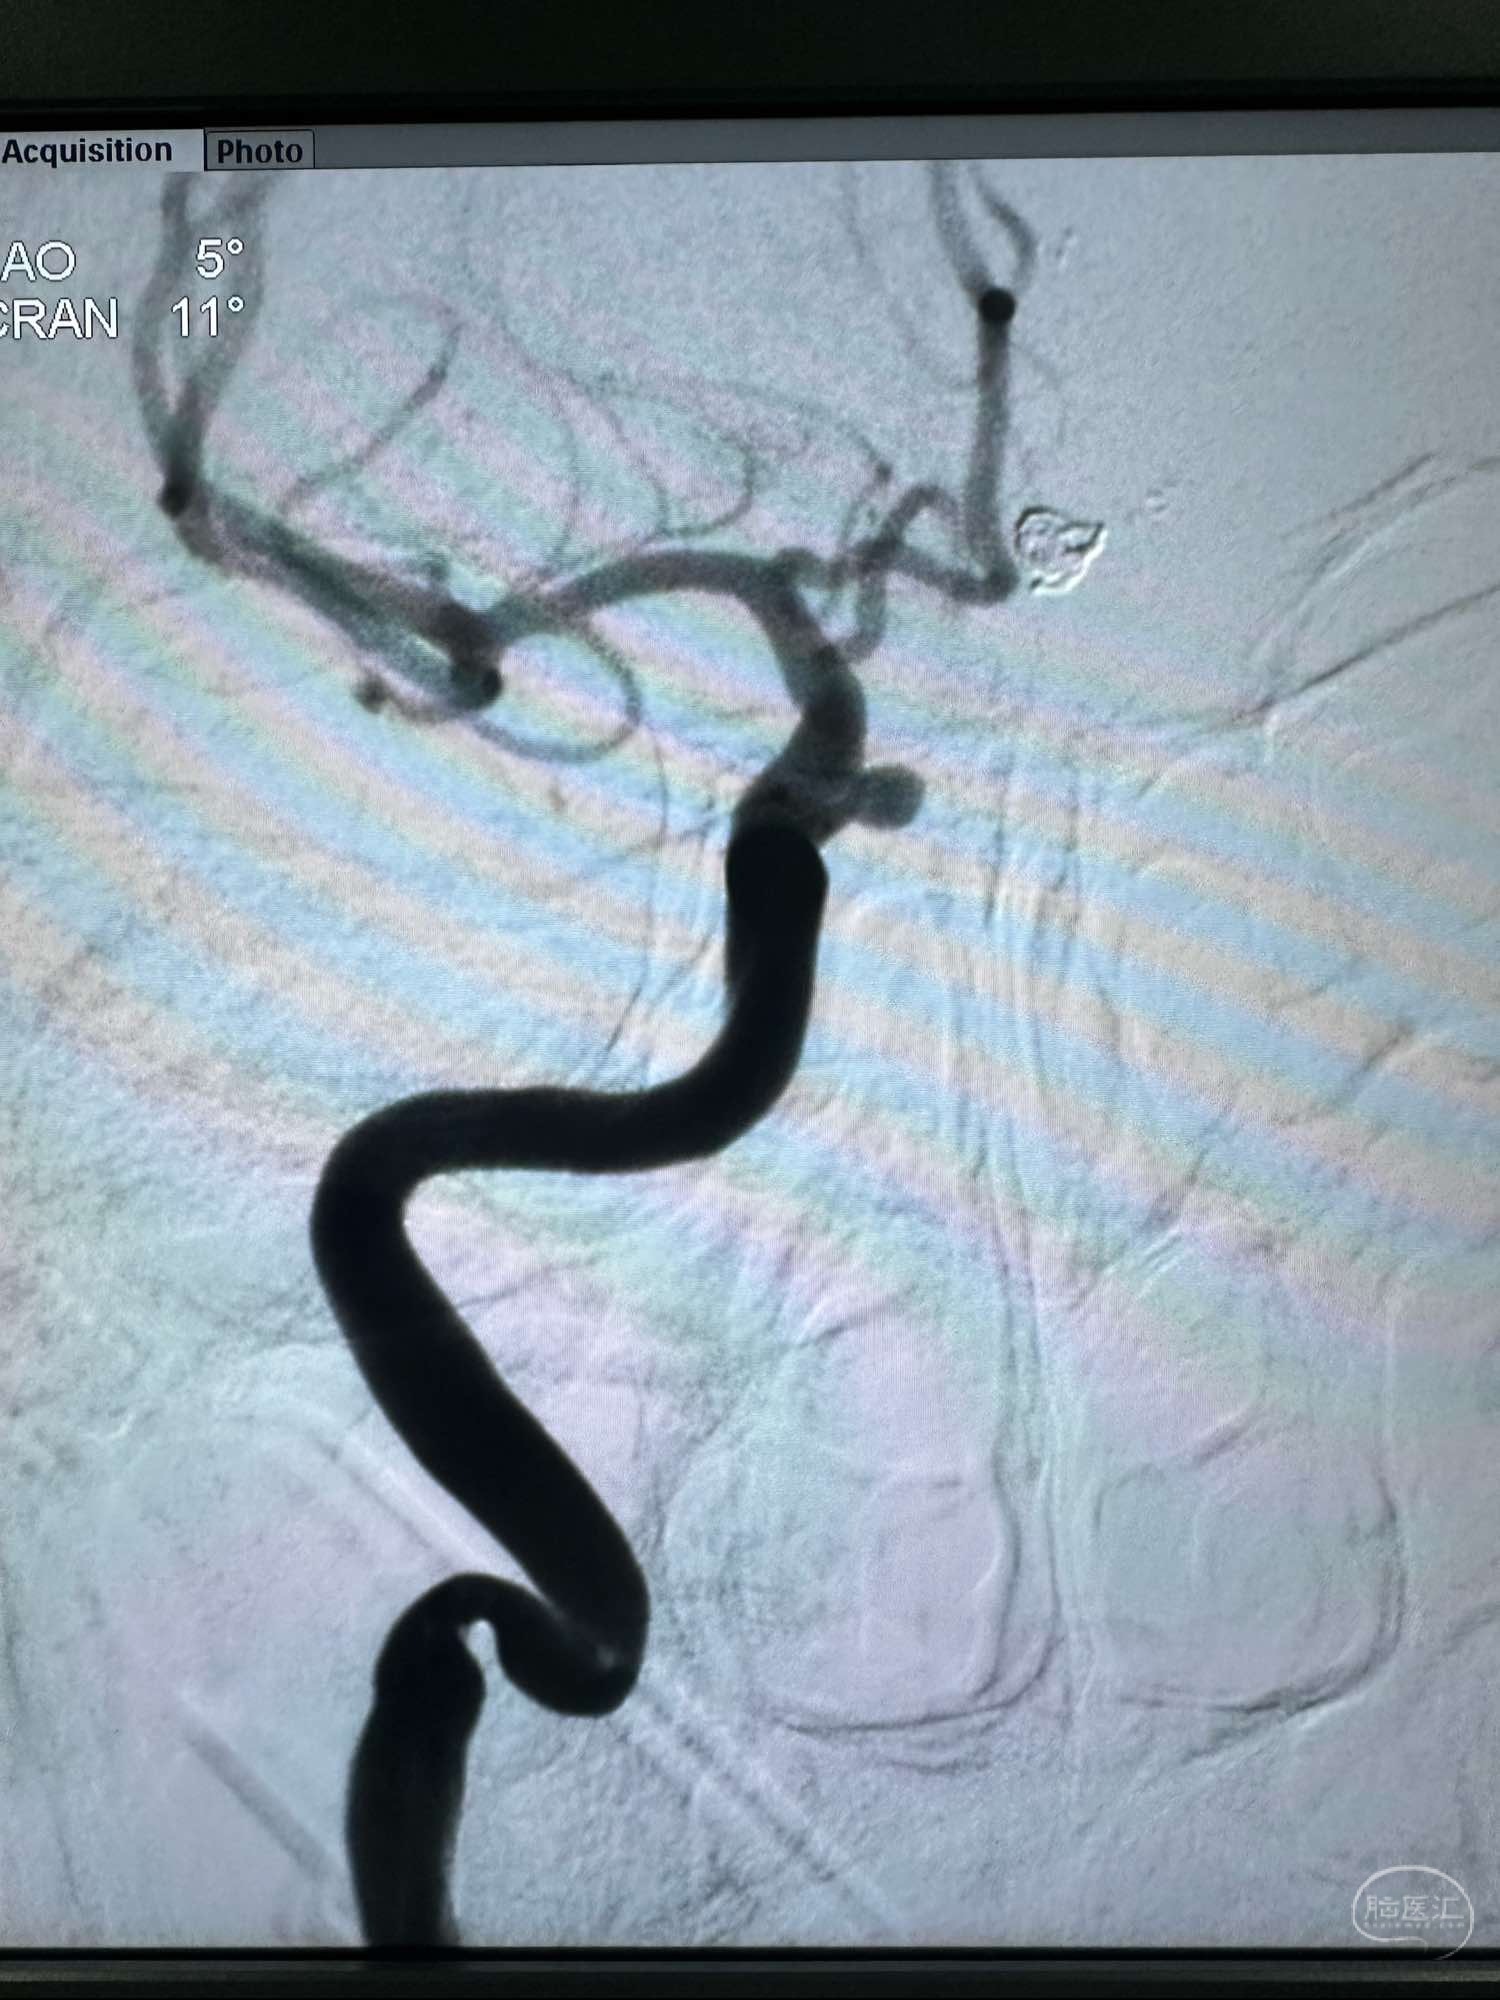

工作角度,路径不好

工作角度,路径不好